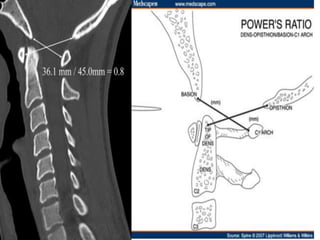

Cephalomedullary angle 135-175

Mid-sagittal diameter: width

1:5 ratio leads to necrosis of gray

matter

• Ogino H: Canal diameter, anteroposterior compression ratio

and spondylotic myelopathy of the cervical spine. Spine 1983;

8:1-15

• Cord compression causes ischemia and direct mechanical

trauma

Mid-sagittal diameter: width 1:5ratio leads to necrosis of gray matter • Ogino H: Canal diameter, anteroposterior compression ratio and spondylotic myelopathy of the cervical spine. Spine 1983; 8:1-15 • Cord compression causes ischemia and direct mechanical trauma